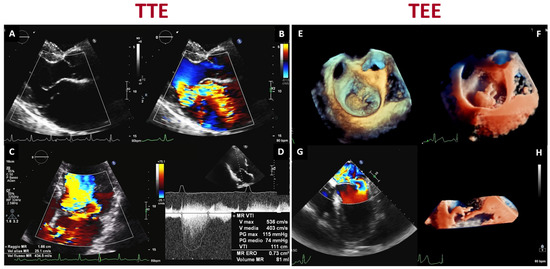

2.1. Echocardiography

3.2. 3D Echocardiography vs. CMR